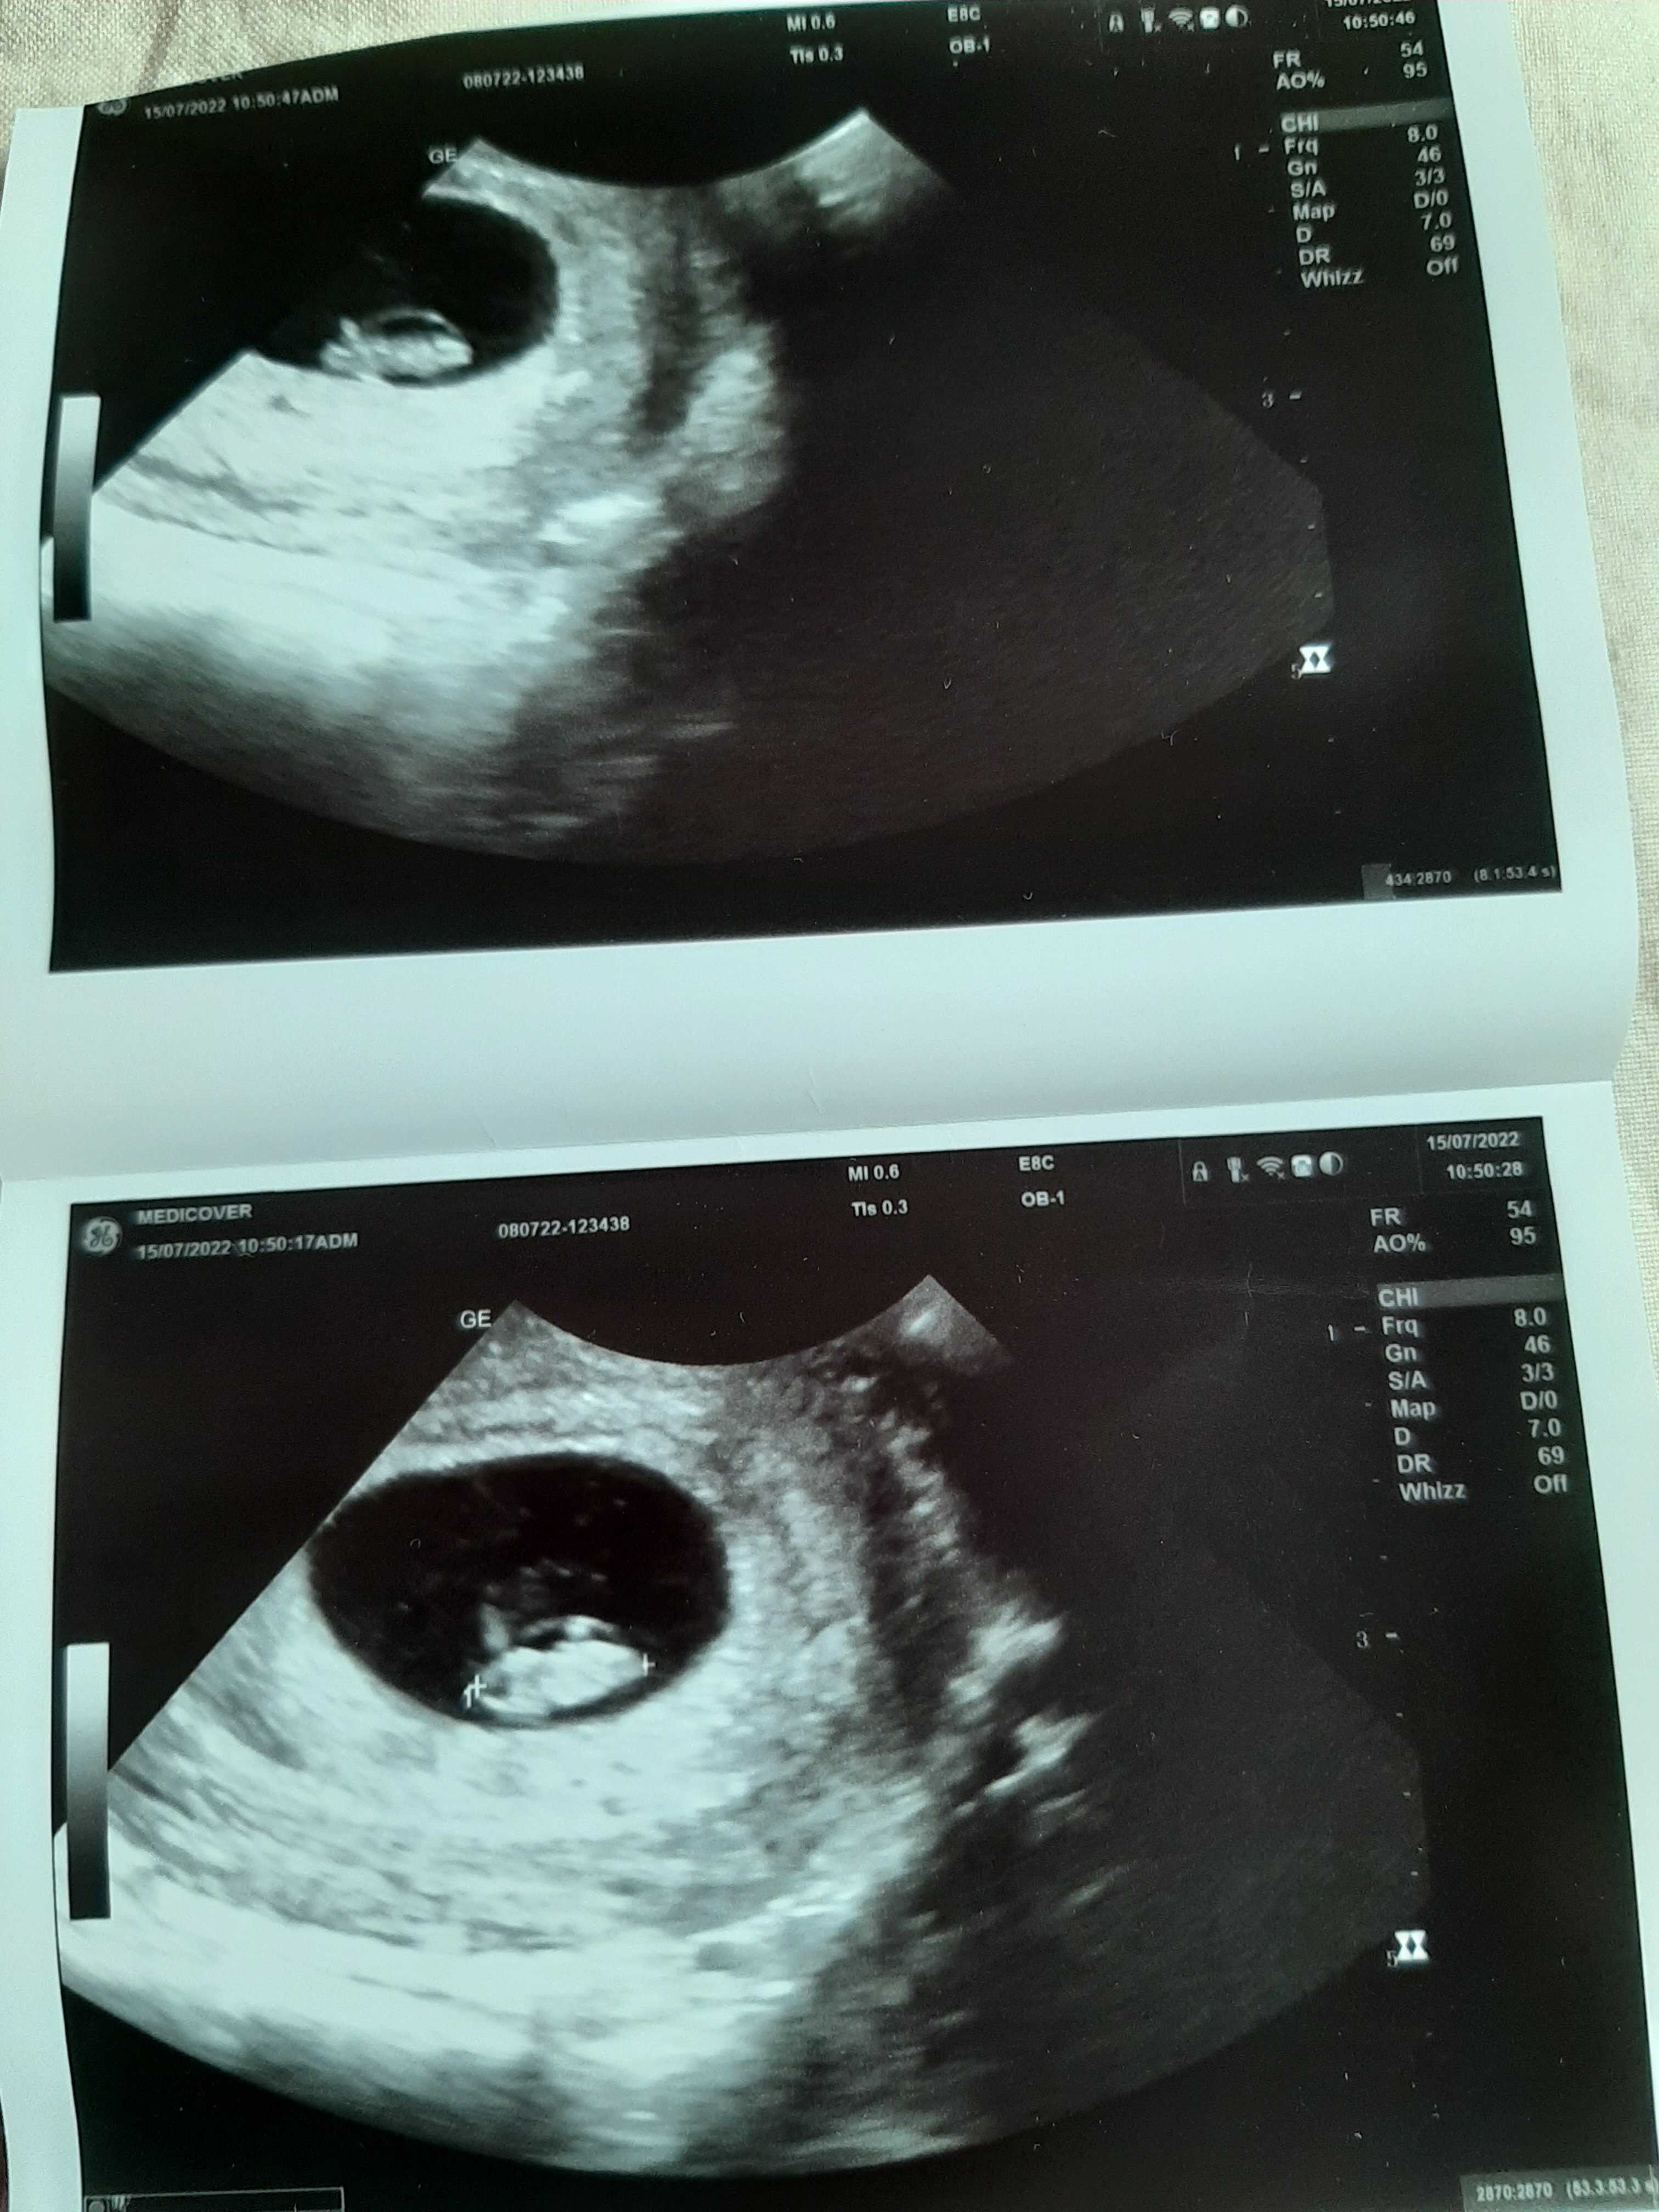

Uffff....Jestem po. Głowa jest, pupa też, coś w środku mrugało, lekarz stwierdził, że serduszko🥰 Ogólnie wszystko w porzadku, rozmiar się zgadza, jedyne co lekarza zaniepokoiło to nadżerka, ale pobrał od razu cytologię i mówił, że póki co się tym nie martwić. Nawet trochę zażartował- mówiłam, że tyle się naczytałam, że po 30 rż tyle rzeczy może być nie tak, a on mi na to "Pani, a po 65 rż? To już nic nie działa tak, jak powinno, będzie tylko gorzej, zobaczy Pani!" A tak serio dodał, że za taką zupełnie bezpieczną granicę uznaje się 35 r.ż. Ledwo, ale się mieszczę🤣 mówił że sushi można, sery też, kawę i herbatę w rozsądnych ilościach, nie polecał solarium, sauny i latania samolotem. Mam brać kwas foliowy i wrócić za 3 tygodnie z wynikami zleconych badań. Ogólnie jestem zadowolona (mimo, że to medicover)😊 a to moja kruszynka🥰Zobacz załącznik 1423964

Uffff....Jestem po. Głowa jest, pupa też, coś w środku mrugało, lekarz stwierdził, że serduszko🥰 Ogólnie wszystko w porzadku, rozmiar się zgadza, jedyne co lekarza zaniepokoiło to nadżerka, ale pobrał od razu cytologię i mówił, że póki co się tym nie martwić. Nawet trochę zażartował- mówiłam, że tyle się naczytałam, że po 30 rż tyle rzeczy może być nie tak, a on mi na to "Pani, a po 65 rż? To już nic nie działa tak, jak powinno, będzie tylko gorzej, zobaczy Pani!" A tak serio dodał, że za taką zupełnie bezpieczną granicę uznaje się 35 r.ż. Ledwo, ale się mieszczę🤣 mówił że sushi można, sery też, kawę i herbatę w rozsądnych ilościach, nie polecał solarium, sauny i latania samolotem. Mam brać kwas foliowy i wrócić za 3 tygodnie z wynikami zleconych badań. Ogólnie jestem zadowolona (mimo, że to medicover)😊 a to moja kruszynka🥰

Tydzień 8, tzn 7+2 wg OM, a na zdjęciu mam 7+1, co by się zgadzało z datą owulacji. Wymiar CRL 1.07 cm (bo to chyba o to chodziło?) A chodzę w Poznaniu, z tym że my mamy wykupiony pakiet u męża w pracy, i to taki troszkę ulepszony.